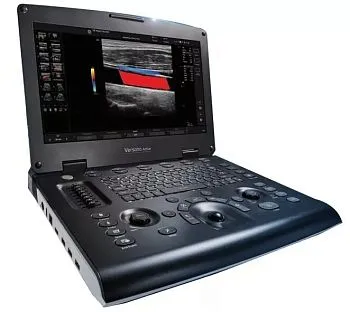

Экспертный LOGIQ P9 Версии R3 и R4 в наличии

Успейте приобрести по выгодной цене

Количество аппаратов ограничено

Официальный дистрибьютор MINDRAY